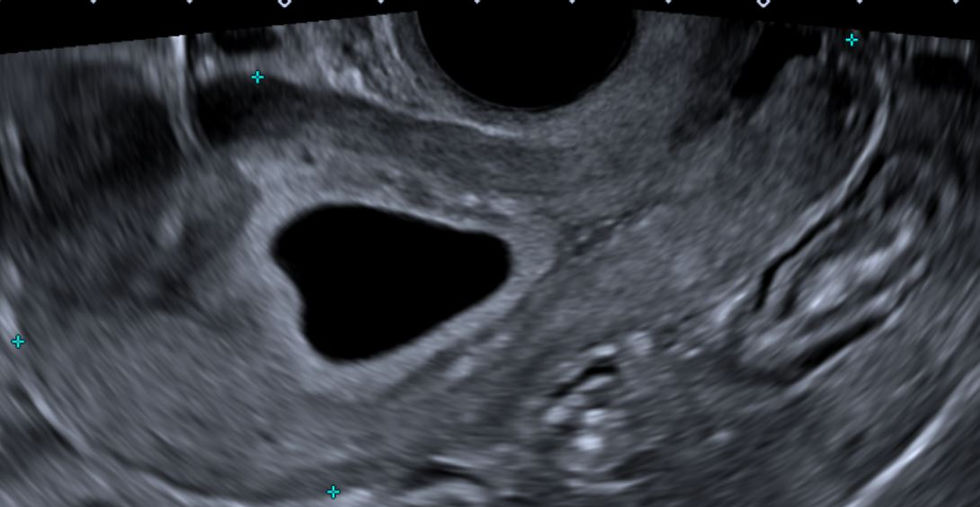

El examen de ecografía obstétrica inicial en Quito, realizada entre la semana 5 y 10 de embarazo (vía Transvaginal), es un momento crucial y emocionante. Esta ecografía temprana permite confirmar la presencia del embrión, verificar su vitalidad detectando el latido cardíaco, determinar la edad gestacional con gran precisión, y evaluar si el embarazo es intrauterino o extrauterino. Es una primera "mirada" a tu futuro bebé.